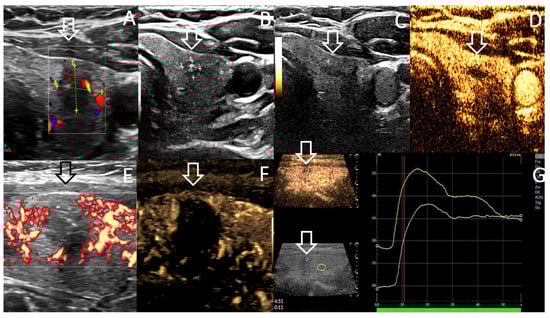

| Color Doppler/MVI/CEUS | Color Doppler/MVI | ||